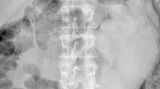

Diese Dinge gehören dort eigentlich nicht hin: Immer wieder passieren Unfälle, wenn Menschen sich zur sexuellen Stimulation über den After Gegenstände in den Darm einführen. Ob Orangen, Spraydosen oder Kaffeebüchsen - der Fantasie sind dabei offenbar keine Grenzen gesetzt.

Die Webseite radiopaedia.org zeigt, welche Dinge Ärzte auf Röntgenbildern schon entdeckt haben. Die Aufnahmen wirken skurril und erschreckend zugleich und machen deutlich, wie weit die eingeführten Dinge bereits in den mescnhlichen Darm vordringen können.

Aber Glück im Unglück für die Patienten: Die Gegenstände können meist ohne Operation entfernt werden. Sehen Sie hier einige der spektakulärsten Röntgenaufnahmen. Da runzeln selbst Chirurgen die Stirn.